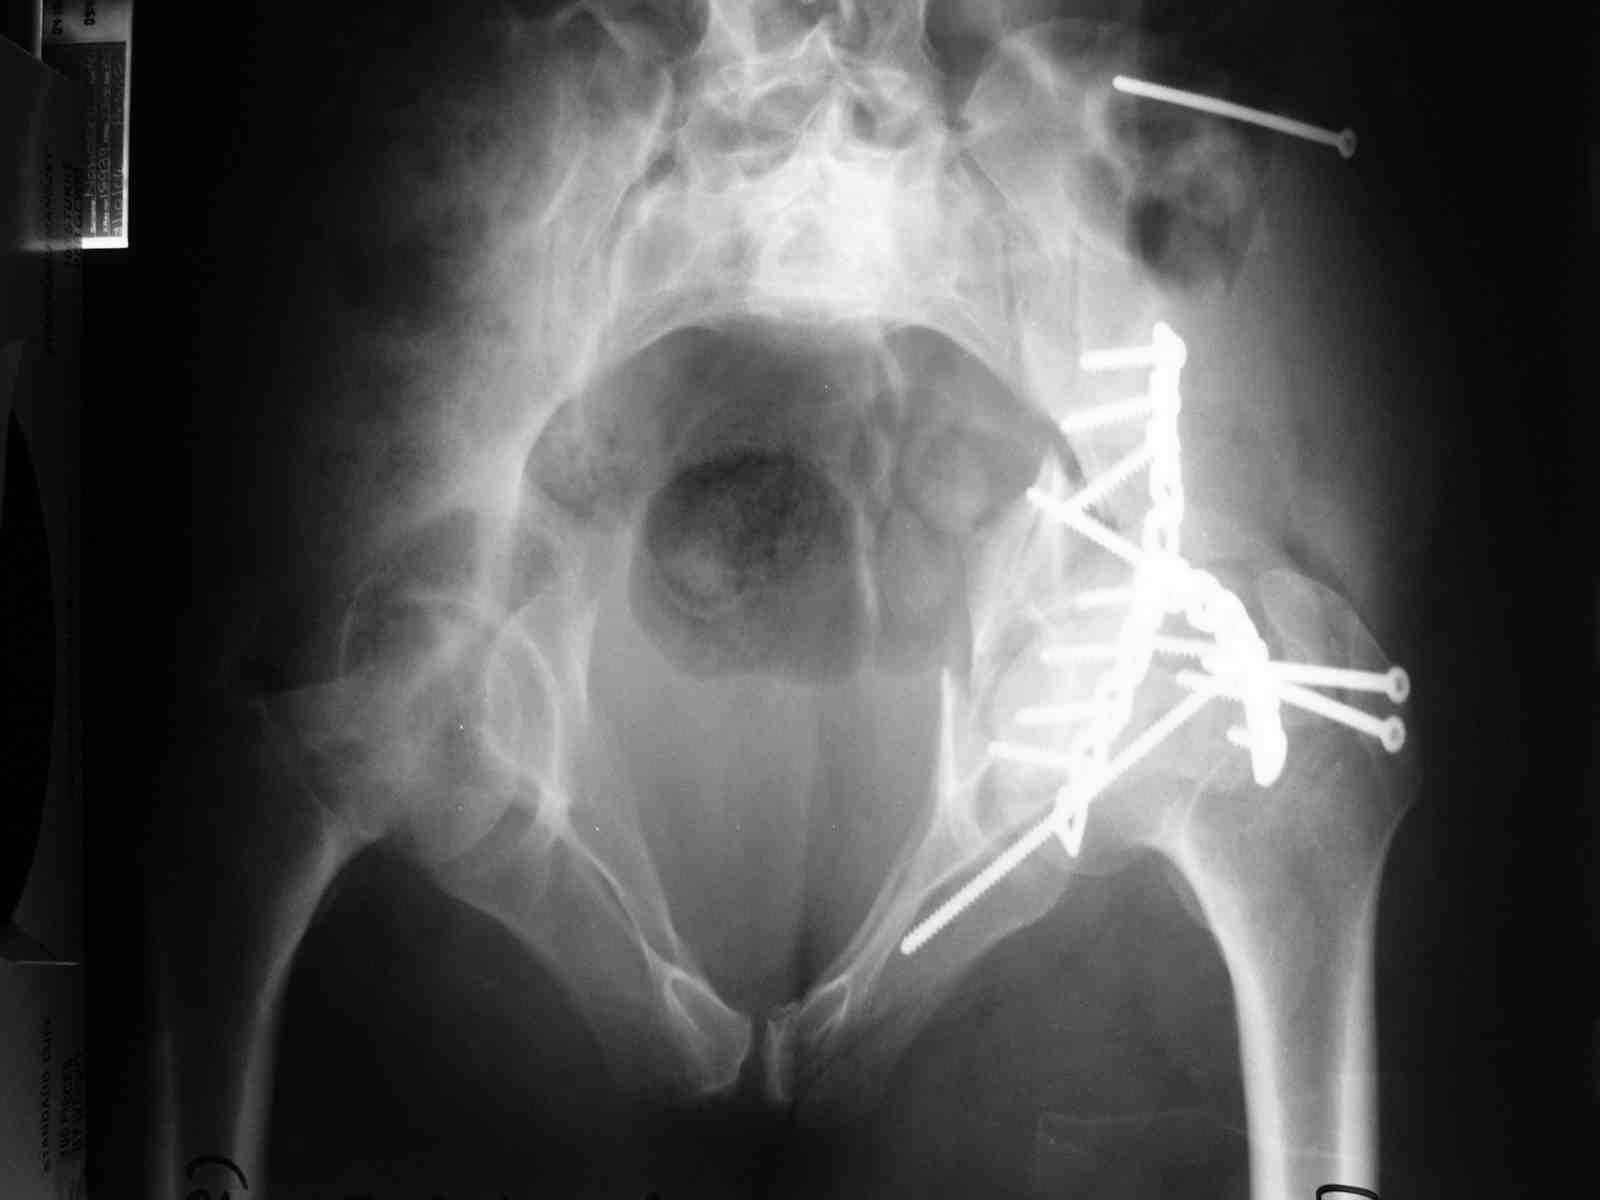

форуме и скелетном вытяжении. С репозицией и фиксацией задней колонны и отдельно задне-верхней стенки впадины проблем не возникло. Послеоп. Рг граммы в приложении. Если возникнут какие-либо дополнения или поправки - был бы признателен.

Причиной обращения к сообществу были возникшие непосредственно после операции сомнения и разочарования полученным качеством репозиции: а надо ли было трогать перелом вообще, репозиция передней колонны технически была очень сложна для меня, хотя реконструкции была в той же последовательности, что Д-р А.В.Рунков рекомендовал, в какой-то момент безуспешных манипуляций стал думать о *вторичной конгруэнтности*, которую не так давно обсуждали на

Вопрос доступа к вертлужной впадине при остеосинтезе задача не простая. Конечно, у Летурнеля и Тайла всё давно описано, нам остается только брать на вооружение. Но сами понимаете, что не бывает двух одинаковых ситуаций, поэтому в каждом случае вопрос решается сугубо индивидуально. Наша главная цель - восстановить анатомию с нанесением минимальной дополнительной травмы тазобедреннному суставу, думаю с этим никто не поспорит. Расширенный илиофеморальный доступ уж слишком травматичен (как сказал один коллега "таз лежит отдельно, больной отдельно").Стоит ли делать из пациента анатомический препарат для того чтобы легче ориентироваться. Да и нужно ли собирать всю "мозаику"? Мы применяли при таких операциях своеобразную операционную хитрость - сначала устраняли грубое смещение крыла под гребнем с фиксацией так называемой "плавающей" пластиной (временно фиксированной на двух винтах)- доступ или продлевали боковой, или делали небольшой дополнительный разрез над гребнем. Это позволяло устранить грубое смещение и захождение отломков тела повздошной кости, что значительно облегчало репозицию и остеосинтез впадины над сводом. Основное внимание конечно же уделяли нагружаемому задне-верхнему отделу. Сообщите ваш адрес, пришлю схемы и рентгенограммы.